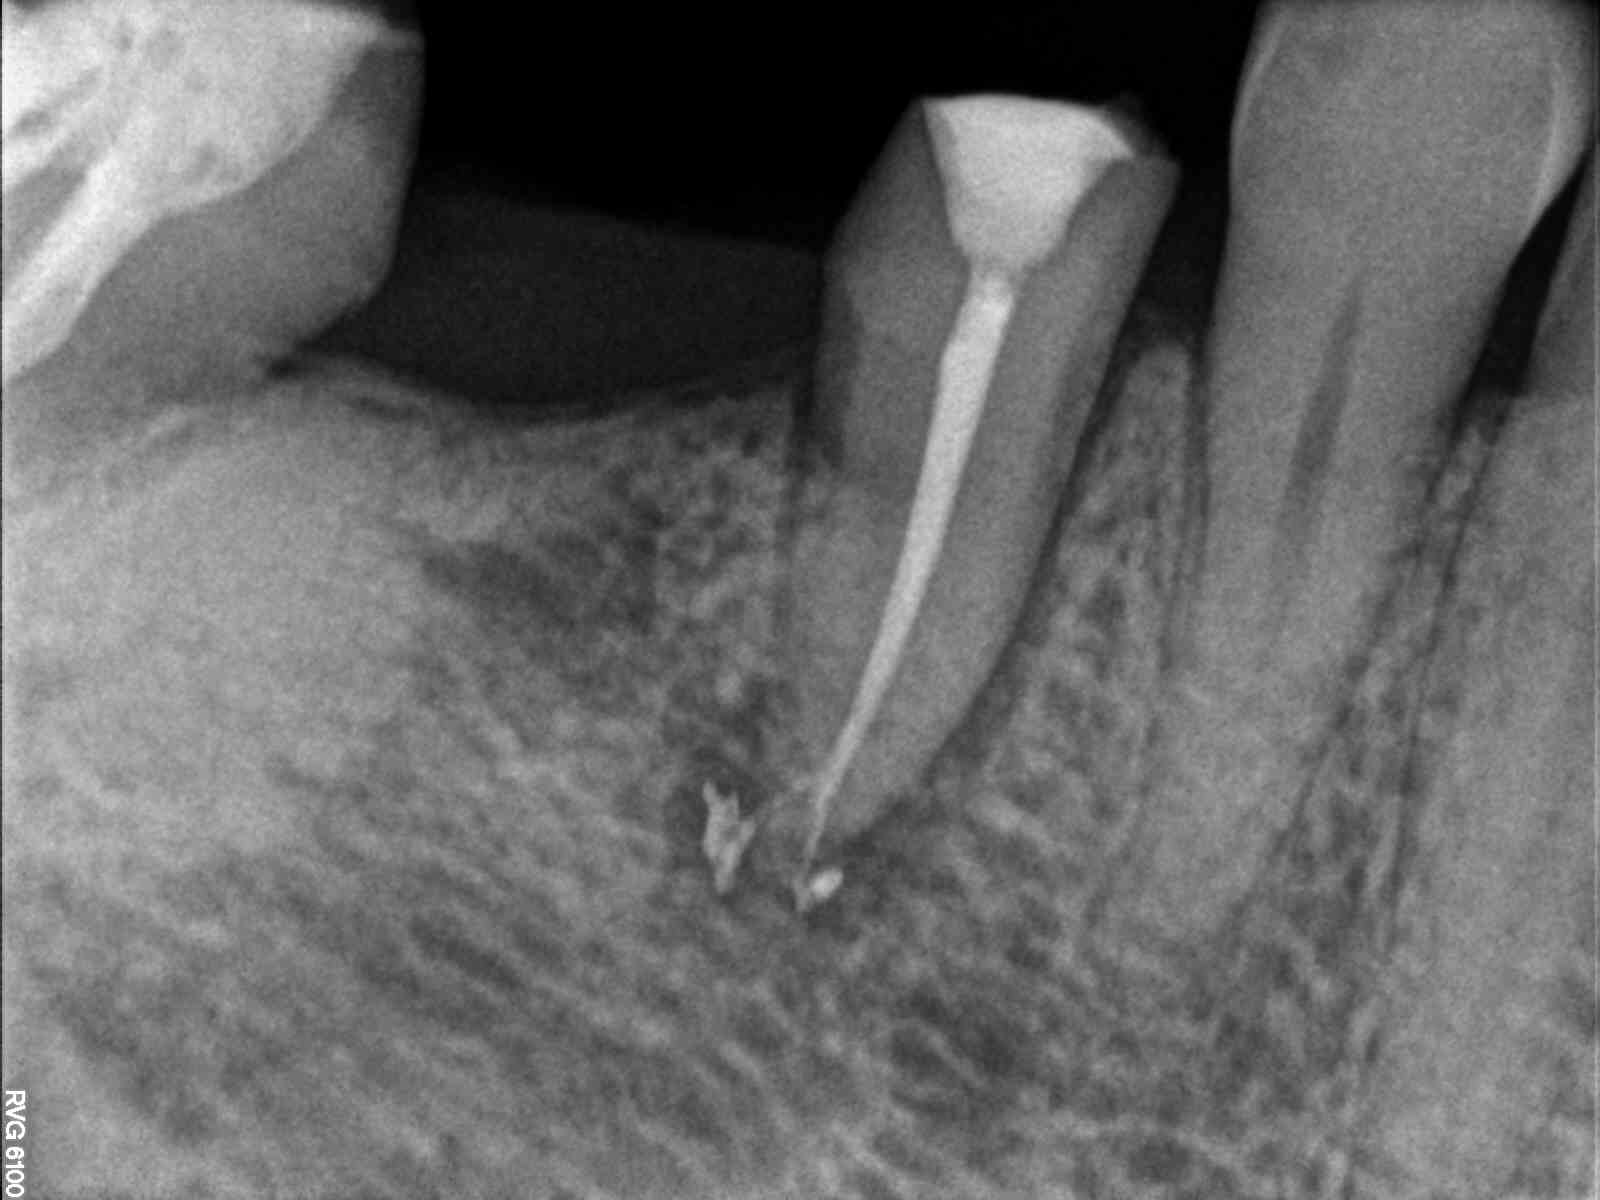

Finalmente  y tras el secado se procedió al sellado del único conducto radicular con cementos de resina de tipo epoxi y técnicas de obturación termoplástica. Así se pudo observar en el control radiográfico la presencia de un delta apical que quedó sellado mientras se realizaba la técnica de sellado del conducto principal como segunda intención y gracias a la aplicación de técnicas de irrigación que eliminan completamente el barrillo dentinario producido durante la preparación mecánica de conductos.